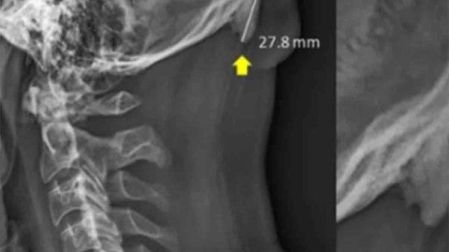

Una investigación publicada en la revista Journal of Anatomy reveló que el uso de los teléfonos celulares está provocando la salida de una especie de cuerno en el cráneo humano.

David Shahar, científico encargado de la investigación, reveló que existe una tendencia al crecimiento de una pequeña protuberancia en forma de pico en el cráneo humano.

Un 41% de los sujetos muestra revelaron el pequeño pico de más de 10 milímetros.